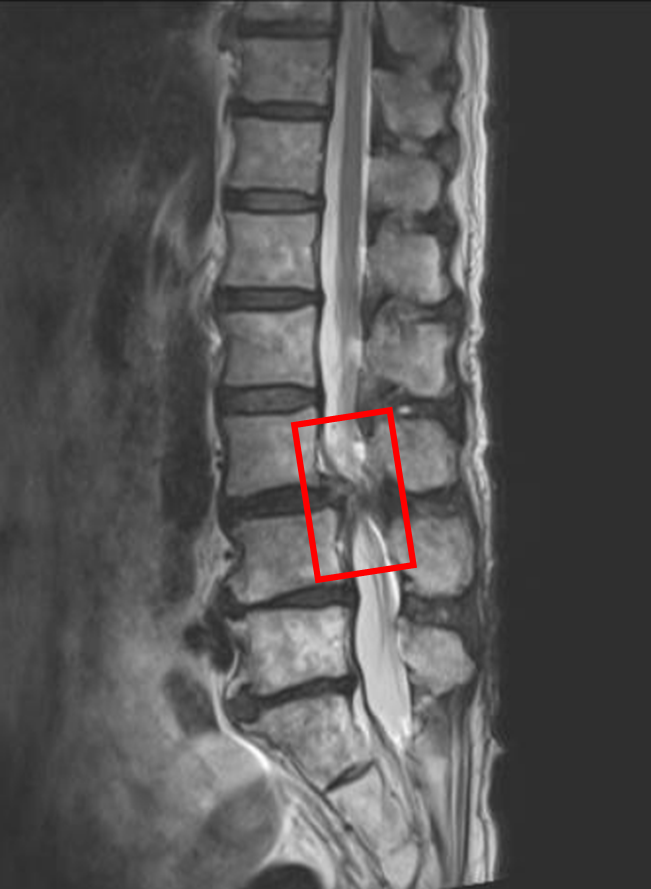

この患者様は赤い枠で示されている箇所(L3/4)に脊柱管狭窄症を認めます。